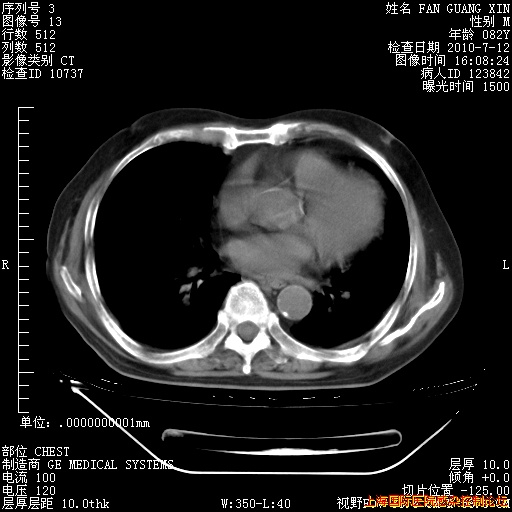

6月12日纵膈窗